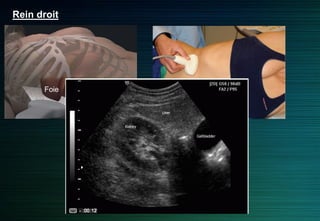

Rein droit

Abord latéral ou antérolatéral

Foie: fenêtre acoustique

(antérolatéral)

Incidence intercostale: pôle supérieur

Foie

Rein